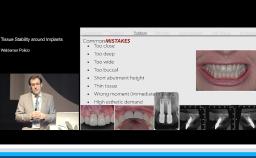

This lecture addresses the clinical challenges of soft and hard tissue defects in the esthetic zone. Dr. Al-Nawas introduces the decision-making process for management of the extraction socket; the advantages and limitations of different biomaterials for ridge preservation; and selection of timing for implant placement and loading based on current literature and recommendations from the 2018 ITI Consensus Conference. Emphases are placed on several important factors: presence of infection, damaged alveolus, soft tissue phenotype, implant position and angulation, implant primary stability, patient expectations, and more. Typical mistakes and complications with immediate implants are also discussed.

recognize the common complications with immediate implants and how to prevent them